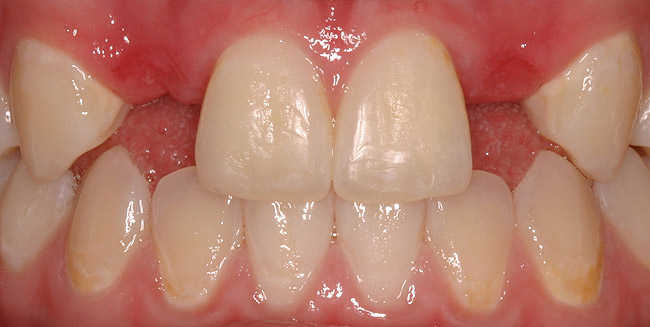

Figure 5a  Congenitally missing lateral incisors. Postorthodontic therapy, prior to implant placement.

Figure 5a

Figure 5b  Congenitally missing lateral incisors. Postorthodontic therapy, prior to implant placement.

Figure 5b

Of all the options presented, when treatment planned and performed to recommended implant surgical and prosthetic guidelines, this option is the most conservative from biological standpoint. The esthetic outcome can be as natural as the tooth it is otherwise replacing (Figure 5).13-15 Patient satisfaction for such successful treatment outcomes is high.16 However, not all patients who are missing a single anterior tooth are ideal candidates for implant therapy. There may be medical contraindications, significant site preparation required, and/or financial constraints. Dental providers may find the resin-bonded or conventional FPD option a more suitable treatment modality with the patient accepting the associated disadvantages and limitations. If this is the case, it is important to have a wider overall treatment outcome picture when comparing the different options.17 From a long-term perspective, few patients perceive real value to either doing nothing or choosing an RPD. Consequently, this leaves the two main contenders: conventional FPD therapy versus single-tooth implant therapy.